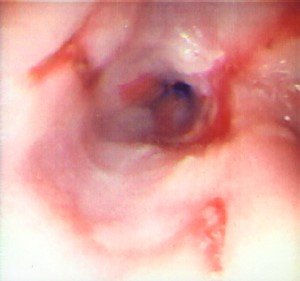

- Endoskopiya - divertikulun perforasiyası təhlükəsinə görə çox ehtiyatla aparılmalıdır.

- Endoskopiya - divertikulun perforasiyası təhlükəsinə görə çox ehtiyatla aparılmalıdır. QB-nun xəstəliklərinin və paraezofageal yırtıqların diferensiasiyası üçün mühümdür.